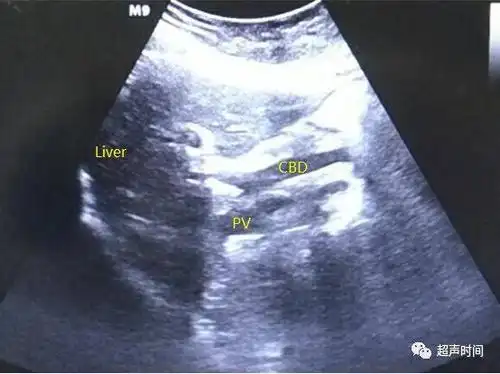

和图 声像图示胆总管(cbd)轻度扩张

(3)肝脏多发小囊肿(见图2c);(4)肝内胆管轻度扩张,建议隔期复查